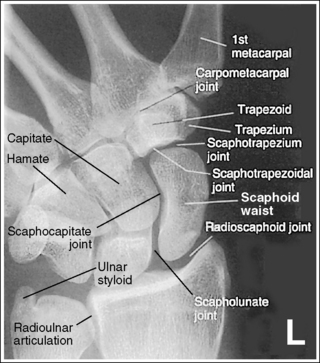

Contrast and density are adequate to demonstrate the scaphoid fat stripe.

• The scaphoid fat stripe is one of the soft tissue structures that should be visible on all scaphoid images (see Figure 4-30). It is convex and located just lateral to the scaphoid in an uninjured wrist.

The scaphotrapezium and scaphotrapezoidal joint spaces are open.

The scaphocapitate and scapholunate joints are open. The ulnar styloid is in profile medially.

The radioscaphoid joint space is open.

The scaphoid is at the center of the exposure field. The carpal bones, the radioulnar articulation, and the proximal first through fourth metacarpals are included within the collimated field.